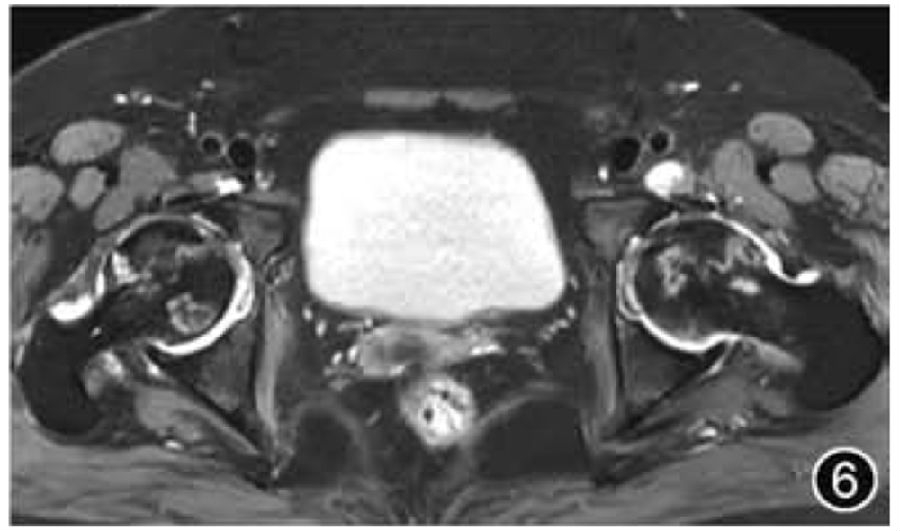

3.FAI:FAI是由股骨近端与髋臼边缘接触碰撞引起,会导致髋臼、盂唇和软骨病变,产生疼痛和功能障碍,并可导致早发性OA。FAI的发病机制可能是由于髋臼较深导致过度覆盖(Pincer型,又称钳夹型)和/或股骨头颈交界处凹陷不足(Cam型,又称凸轮型)导致,两种解剖异常多同时出现(混合型)。FAI的影像学管理和评估应首先进行前后位骨盆X线平片检查,有症状患者应进行蛙式位检查及CT检查,以全面评估髋臼及股骨头颈部形态。MRI也是全面评估FAI的重要手段,主要侧重于评估盂唇、软骨的损伤程度及范围,前盂唇是FAI的主要损伤部位(图4)。需要注意的是,只有当典型的影像学特征与临床症状同时出现时,才能做出FAI的诊断。

图4 髋关节撞击MRI图像。冠状面T2WI示髋臼外上盂唇撕裂(短↑)伴有股骨头颈交界处骨髓水肿(长↑)